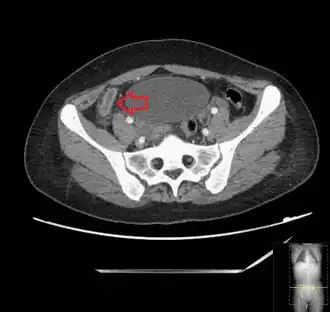

Diagnosis

_(Radiopaedia_154713-127660_Axial_1).jpg.webp)

Diagnosis is based on a medical history (symptoms) and physical examination, which can be supported by an elevation of neutrophilic white blood cells and imaging studies if needed. Histories fall into two categories, typical and atypical.

In children the clinical examination is important to determine which children with abdominal pain should receive immediate surgical consultation and which should receive diagnostic imaging.[40] Because of the health risks of exposing children to radiation, ultrasound is the preferred first choice with CT scan being a legitimate follow-up if the ultrasound is inconclusive.[41][42][43] CT scan is more accurate than ultrasound for the diagnosis of appendicitis in adults and adolescents. CT scan has a sensitivity of 94%, specificity of 95%. Ultrasonography had an overall sensitivity of 86%, a specificity of 81%.[44]

Computed tomography

Where it is readily available, computed tomography (CT) has become frequently used, especially in people whose diagnosis is not obvious on history and physical examination. Concerns about radiation tend to limit use of CT in pregnant women and children, especially with the increasingly widespread usage of MRI.[49][50]

The accurate diagnosis of appendicitis is multi-tiered, with the size of the appendix having the strongest positive predictive value, while indirect features can either increase or decrease sensitivity and specificity. A size of over 6 mm is both 95% sensitive and specific for appendicitis.[51]

However, because the appendix can be filled with fecal material, causing intraluminal distention, this criterion has shown limited utility in more recent meta-analyses.[52] This is as opposed to ultrasound, in which the wall of the appendix can be more easily distinguished from intraluminal feces. In such scenarios, ancillary features such as increased wall enhancement as compared to adjacent bowel and inflammation of the surrounding fat, or fat stranding, can be supportive of the diagnosis. However, their absence does not preclude it. In severe cases with perforation, an adjacent phlegmon or abscess can be seen. Dense fluid layering in the pelvis can also result, related to either pus or enteric spillage. When patients are thin or younger, the relative absence of fat can make the appendix and surrounding fat stranding difficult to see.[52]